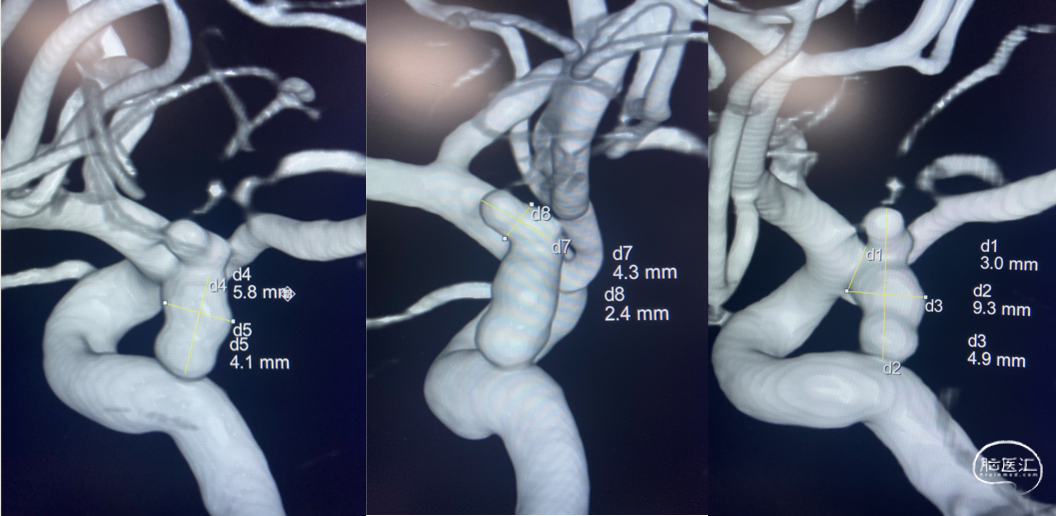

左侧颈内动脉后交通段动脉瘤整体大小约4.9mm×9.3mm,

子瘤约4.3mm×2.4mm,

主瘤体5.8mm×4.1mm,

瘤颈宽3.0mm,不规则